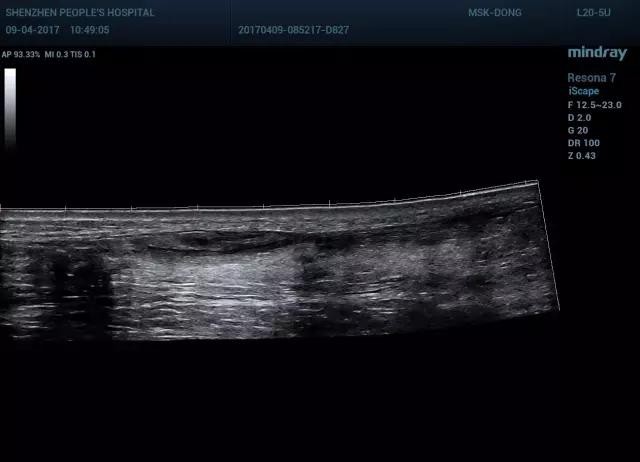

图5跟腱短轴宽景成像

图6 跟腱部分撕裂长轴宽景成像(可见跟腱塌陷,连续性中断)